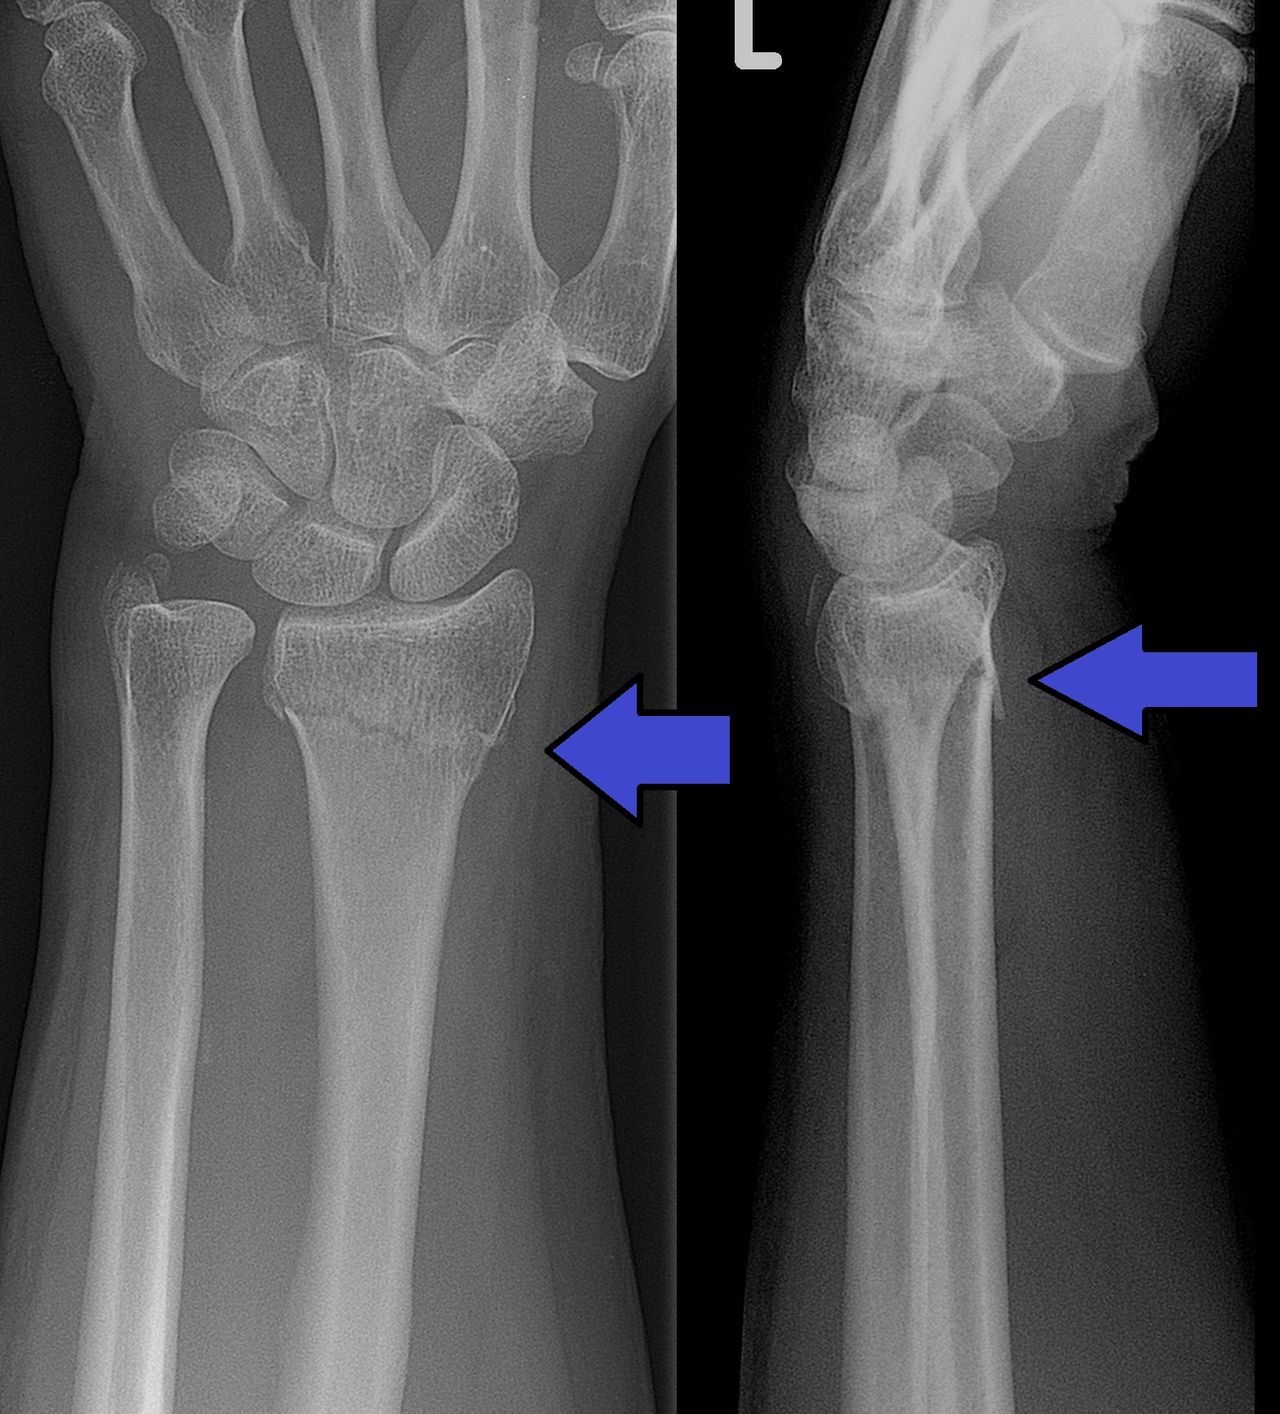

AI som kan upptäcka frakturer godkänd i USA Det kommer bli mycket AI inom sjukvården i framtiden AI som kan upptäcka frakturer godkänd i USA AJ! Foto: Lucien Monfils / Wikipedia Det amerikanska läkemedelsverket FDA har godkänt ett AI-baserat system för att upptäcka frakturer i patienters handleder.Systemet kallas för OsteoDetect och AI:n är tränad för att upptäcka så kallade distala radiusfrakturer, det som vi vanligtvis kallas för handledsfrakturer eller handledsbrott. Tanken med systemet är inte att det ska ersätta läkare utan OsteoDetect ska istället användas som ett komplement när läkaren ställer sin diagnos.Tidigare i år har FDA bland annat godkänt AI-baserade system för att upptäcka ögonsjukdomar såväl som att upptäcka stroke-fall. fda.gov Pryl, Artificiell intelligens, frakturer, sjukvård, benbrott, OsteoDetect, imagen Via engadget.com